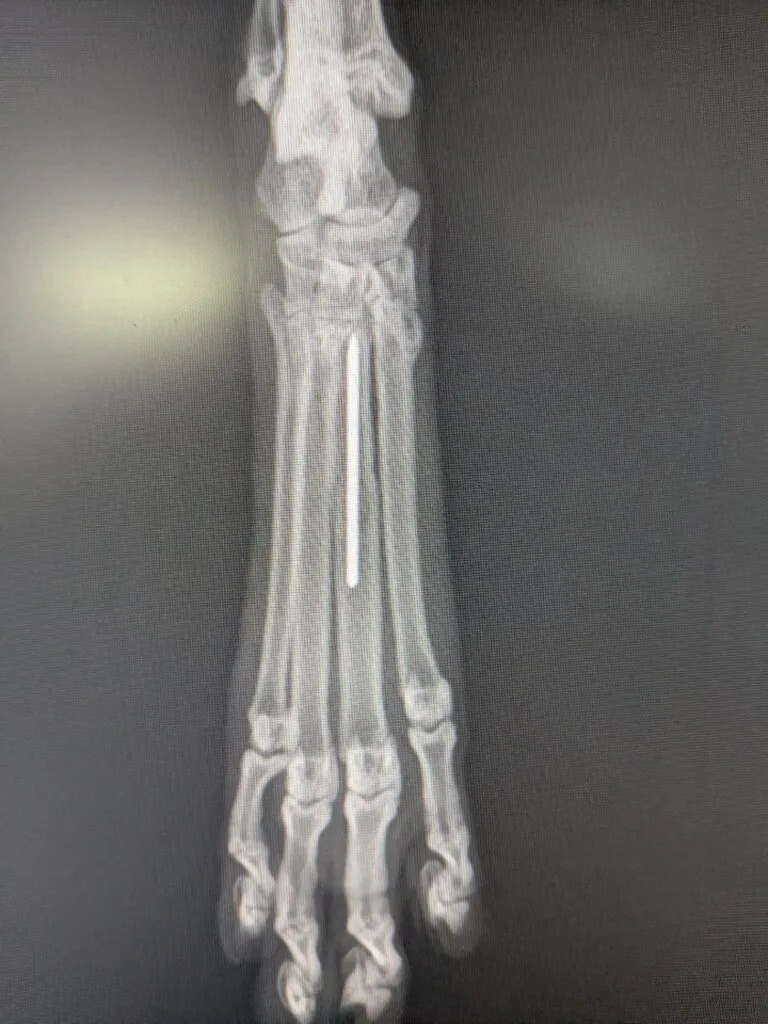

そのため、今回は髄内ピンといって、骨の中心に金属製のピンを埋める方法で行いました。

術後のレントゲン画像です。

1本のみの髄内ピンは弱点の多い固定方法です。骨が曲がる力に対する抵抗力はありますが、骨どうしの圧迫や回転に対しては強度が全くありません。

そもそも中足骨に入れる程度の太さの髄内ピンだと曲がる力に対する抵抗力も少なく、どちらかというと骨がずれないようにアライメントを整えているだけというイメージになります。

そのため、基本的にはギブスによる外固定の併用が必須となります。

ただ、今回は幸いにも他の中足骨が折れておらず、それらがギブスの役割も果たしてくれるため、少し安心です。